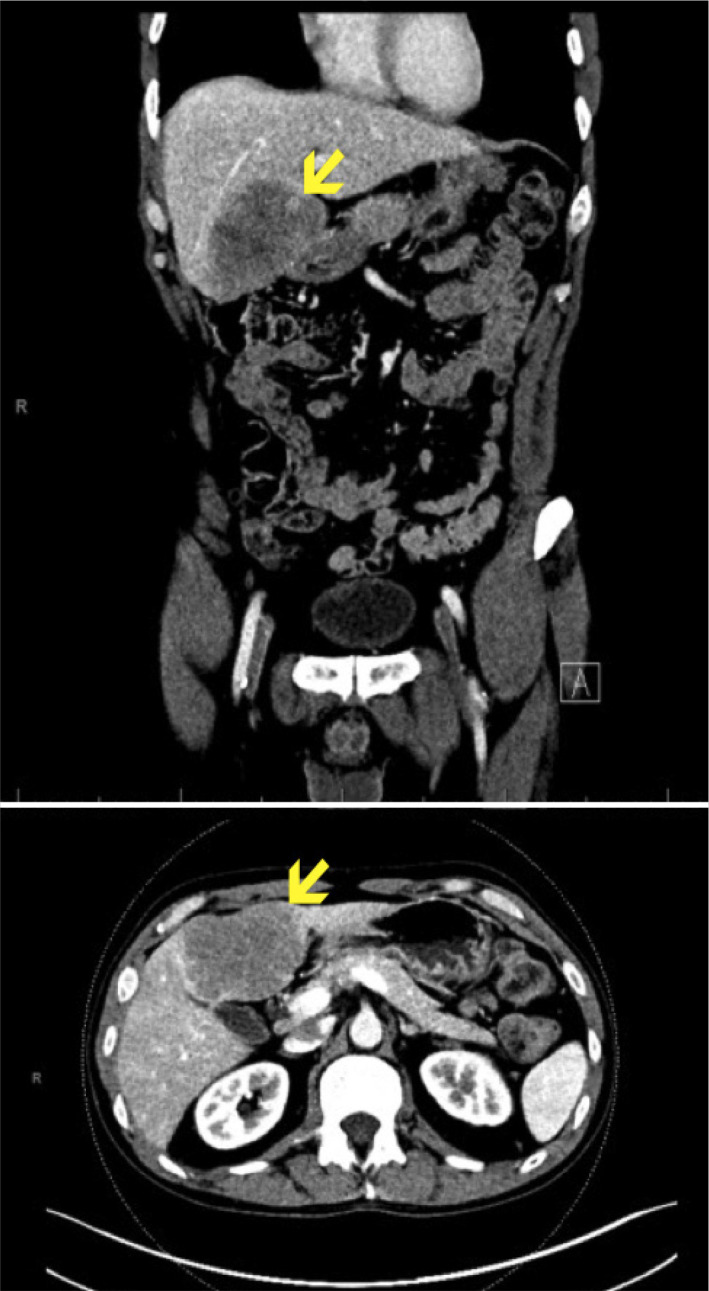

Primary Biliary Cholangitis (PBC) is a chronic cholestatic liver disease that can lead to cirrhosis and the development of hepatocellular carcinoma. PBC is not known to be associated with hepatic angiosarcoma. Second-line treatments for PBC, including obeticholic acid, have had less than a decade of clinical use. We present a case of a patient with PBC treated with obeticholic acid who subsequently developed hepatic angiosarcoma. The patient is now on active surveillance following resection of the angiosarcoma. The development of this rare and aggressive cancer should prompt closer post-marketing surveillance for obeticholic acid.